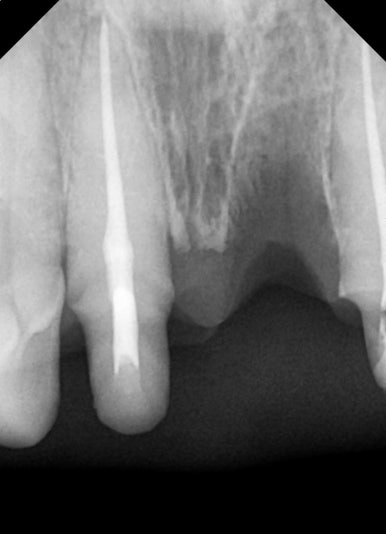

남아 있는 앞니의 신경치료를 안전하게 마무리 한 모습

이후, 뿌리만 남은 치아는 발치를 하였고, 잇몸이 회복되는 동안

양옆의 치아를 신경치료 진행하였습니다.

치아에 금이 가있던 치아는

치아머리 부분의 안정화를 위해 "포스트 Post"라는 과정까지 진행하였습니다.